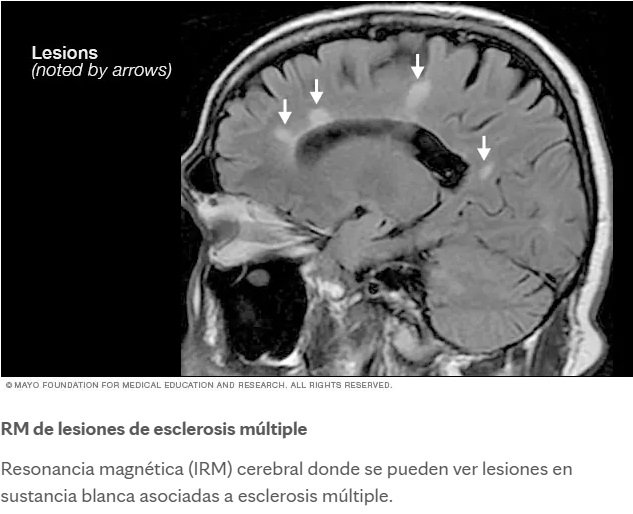

- Lesiones en lóbulos frontales, cuerpo calloso, ganglios basales y sustancia blanca subcortical se han relacionado con síntomas depresivos, apáticos y cognitivos.